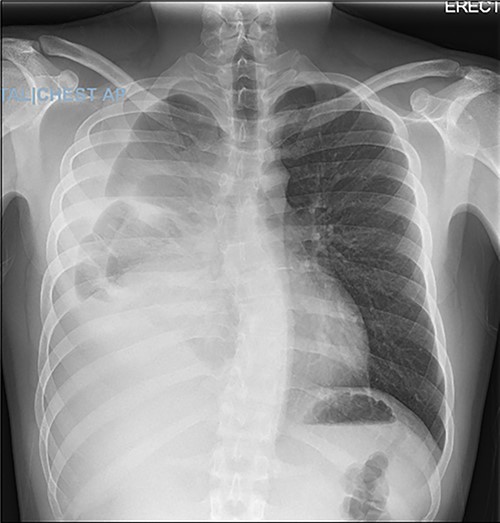

A 22-year-old male patient with no significant medical or surgical history and no smoking history presented to the emergency department for evaluation of persistent cough for 3 weeks. The cough was initially associated with chest pain, which then subsided. He denied fever, chills, nasal congestion, shortness of breath and sore throat. A viral panel including COVID-19 was negative and patient was vaccinated against COVID-19. Chest X-ray (Fig. 1) demonstrated a large right pleural effusion with right lower lung consolidation. To further investigate the chest X-ray findings, a computed tomography (CT) of the thorax (Fig. 2) was performed, revealing a 17.2 cm mass occupying the right hemithorax causing a leftward mediastinal shift and narrowing of the right-sided bronchi. To better determine the etiology of the mass, a biopsy was obtained via CT-guided fine needle aspiration. Although analysis of this specimen exhibited mostly necrotic material, it also showed nests of monomorphic epithelial-like cells with many small mature lymphocytes and findings consistent with a thymic neoplasm. Germ cell tumor markers were negative. The beta-hCG, AFP and LDH markers were also negative. However, a more definitive diagnosis was unable to be determined due to the scant amount of collected specimen. Given the clinical, radiographic and pathologic findings, the patient was scheduled for resection of the mass.

Axial view of CT of thorax with intravenous contrast demonstrating large enhancing and heterogenous mass of the right hemithorax; right-sided pleural effusion is also seen.